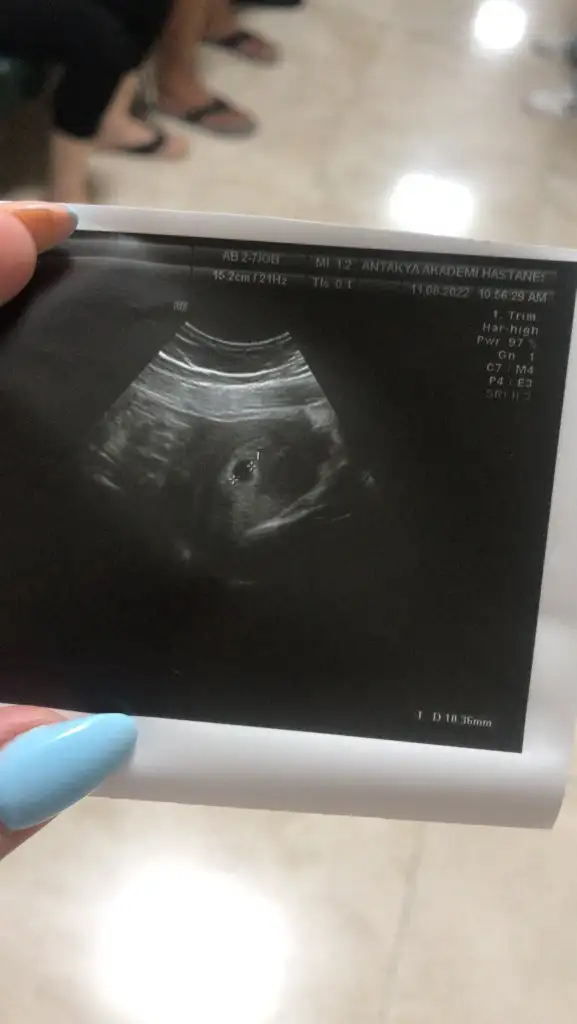

Çok şükür..kalb atışına ne zaman çağırdı?Kızlar selam bugün keseyi gördük 10 mm. Yolk kesesi bulanık dedi kese sınırları düzenli dedi. 5+5 im ama ben 18. Günde yumurtladm. Yolk yok deyince ben bi panik oldum. Kesenin fotosunuda atıyormEki Görüntüle 3111305

Oy maşallah minnoşaKızlar selam bugün keseyi gördük 10 mm. Yolk kesesi bulanık dedi kese sınırları düzenli dedi. 5+5 im ama ben 18. Günde yumurtladm. Yolk yok deyince ben bi panik oldum. Kesenin fotosunuda atıyormEki Görüntüle 3111305

Ya canımm cidden görünüyor muu? Ben ağlıyorm saatlerdirOy maşallah minnoşayolk görünüyo canım panik yapma. Ay erkek hissettim, yusyuvarlak kese